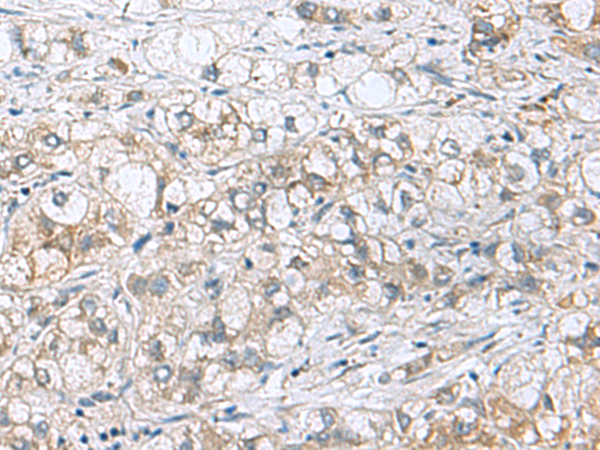

分类: 科研抗体货号: P10251别名: MOM1; PLA2; PLA2B; PLA2L; PLA2S; PLAS1; sPLA2应用: IHC反应种属: Human